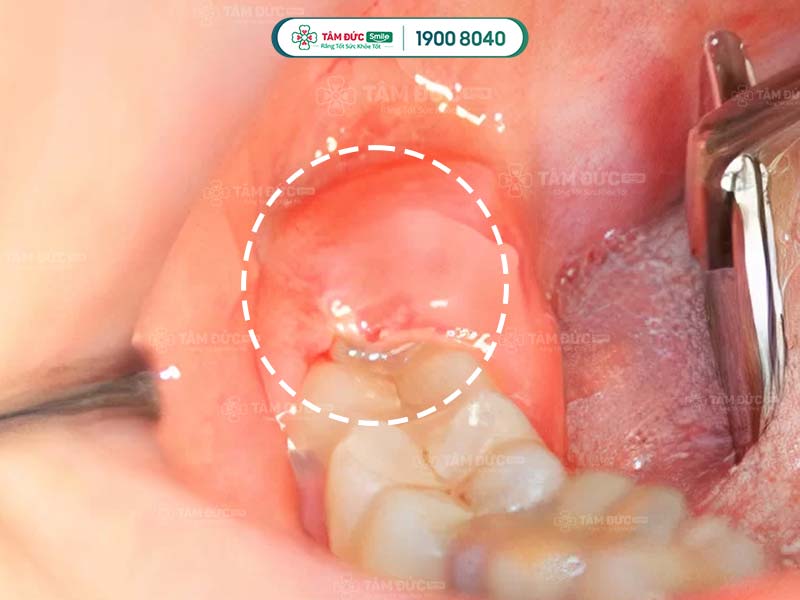

1.3. Đau do chấn thương mô mềm

Khi nhổ răng khôn, vùng má, vòm miệng, nướu, hàm…là những mô mềm rất dễ bị tổn thương. Nếu Quý khách bị chấn thương mô mềm, tình trạng đau nhức có thể kéo dài tới vài tuần. Những cơn đau dai dẳng, âm ỉ tạo cảm giác khó chịu, ảnh hưởng nghiêm trọng tới sức khỏe.

nhổ răng khôn 2 tuần vẫn đau do bị chấn thương mô mềm

Chấn thương mô mềm có thể gây đau đớn kéo dài